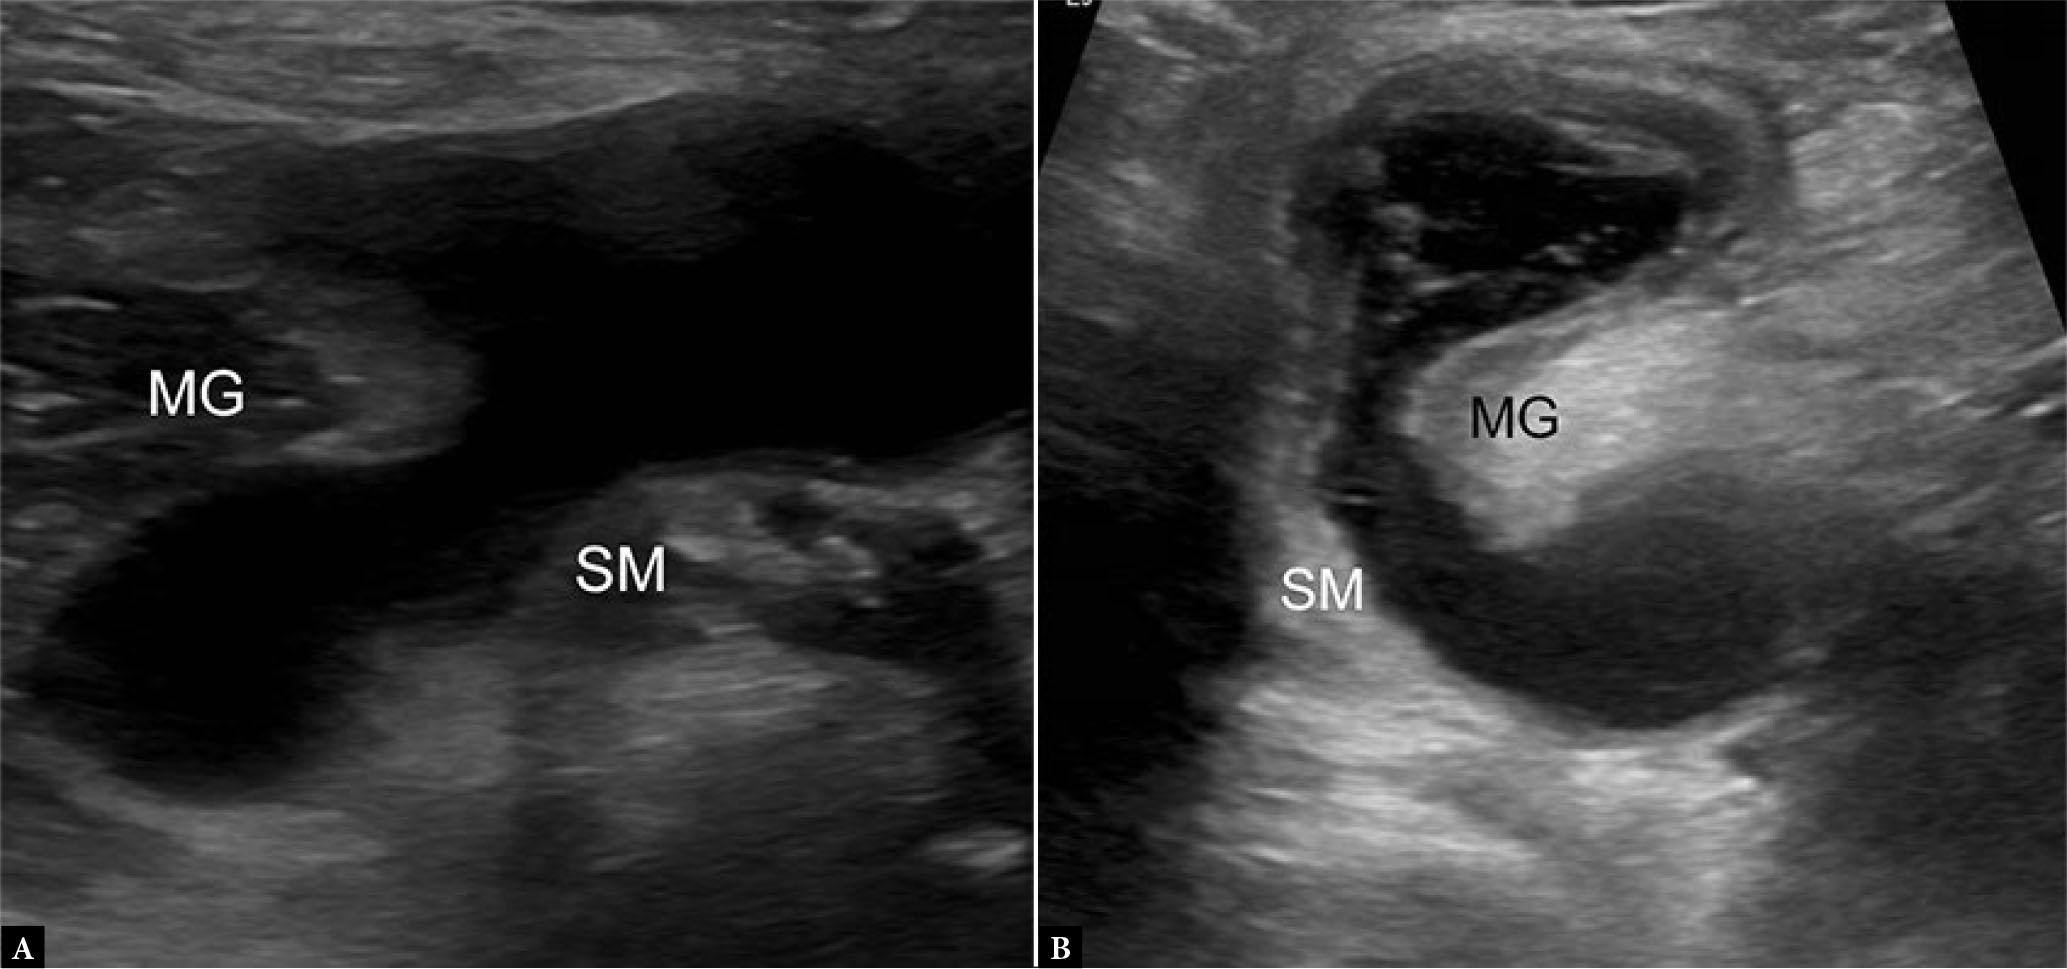

Popliteal fossa masses are one of the most common indications for knee US, and examination typically reveals a Baker (or popliteal) cyst in the characteristic location between the semimembranosus and medial head of gastrocnemius tendons (Fig. 17 A)(2). The cyst, actually the combination of the gastrocnemio-semimembranosus and subgastrocnemius bursae, may demonstrate evidence of internal complexity, such as septations, debris, joint bodies, as well as partial or complete rupture with associated tracking fluid and irregular cyst margins (Fig. 17 B)(7). Other common cystic masses include ganglia, synovial cysts, and parameniscal cysts, as well as additional bursae.

Fig. 17.

A. 19-year-old male with Baker’s cyst. Transverse grayscale US image of the posterior knee shows bilobed anechoic fluid collection located between the semimembranosus (SM) and medial gastrocnemius (MG) tendons, consistent with a Baker’s cyst. Note anisotropy of the SM relative to MG tendon, not to be confused with debris. B. 85-year-old female with complex Baker’s cyst. Transverse grayscale US image shows thick-walled collection with internal septations and debris with otherwise typical location and appearance